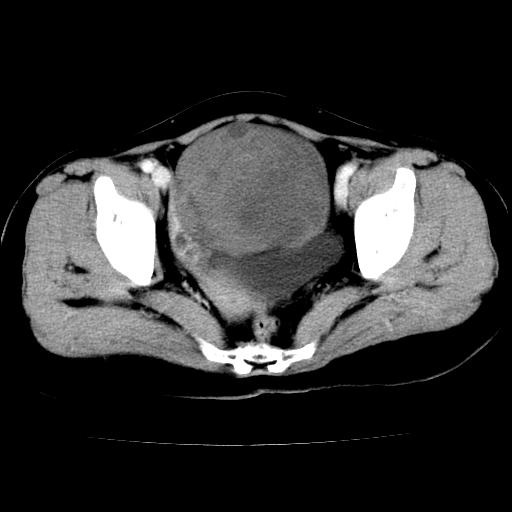

标题: CT24785:女,62岁,发现下腹部肿物半年。 [打印本页]

标题: CT24785:女,62岁,发现下腹部肿物半年。

女,62岁,发现下腹部肿物半年,下腹部不适。

考虑肠系膜间质肉瘤或脐尿管癌可能性大。

卵巢囊腺瘤或囊腺癌,建议免疫组化实验

卵巢囊腺瘤或囊腺癌可能。